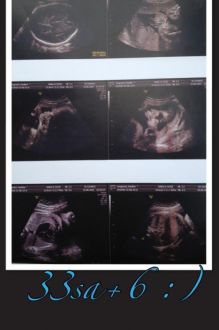

Troisieme écho Ça y est dernière écho de passer avant la grande rencontre du jour J :D ! Donc bébé se porte a merveille il est déjà en mode prêt a sortir tête en bas et dos a gauche bref parfait ! Il pèse 2kg330 et mesure 46,5cm déjà ! Bref un sacré Loulou ! Il est estimé a 3kg800 voir plus a terme et 52cm... Un beau bébé grassouillet comme je les aimes... Prochain rdv la semaine prochaine et ensuite le dernier mois je serai suivi toutes les semaines au bloc obstétricale ce que je trouve super j avais pas eu ça a mon premier et si col favorable je peux décider d avoir un déclenchement quand je veux et il ne force pas c'est juste une proposition :) bref j adore cette maternité lol ! Allez et demain a moi les 34sa ça vient petit a petit et demain on passe a J-49 encore une dizaine en moins !!!  Message déposé le 13.06.2013 à 14:07 - Commentaires (6)